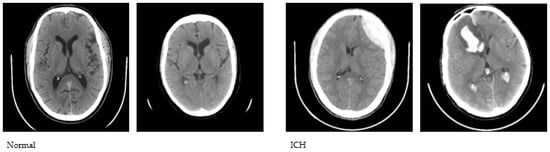

We used the publicly available CQ500 database to conduct this study. The CQ500 dataset [27] includes CT scans of 491 subjects that were employed to construct a Convolutional Neural Network (CNN)-based model for the classification of hematoma subtypes, calvarial fractures, and midline shift in a fully automated fashion. We used a total of 1831 CT images, of which 1000 are healthy and 831 are with hematoma. The CT images were initially converted to JPG format with a 512 × 512 dimension. A sample set of normal and abnormal axial CT images is shown in Figure 1.

Figure 1.

Sample CT images used to conduct the study.